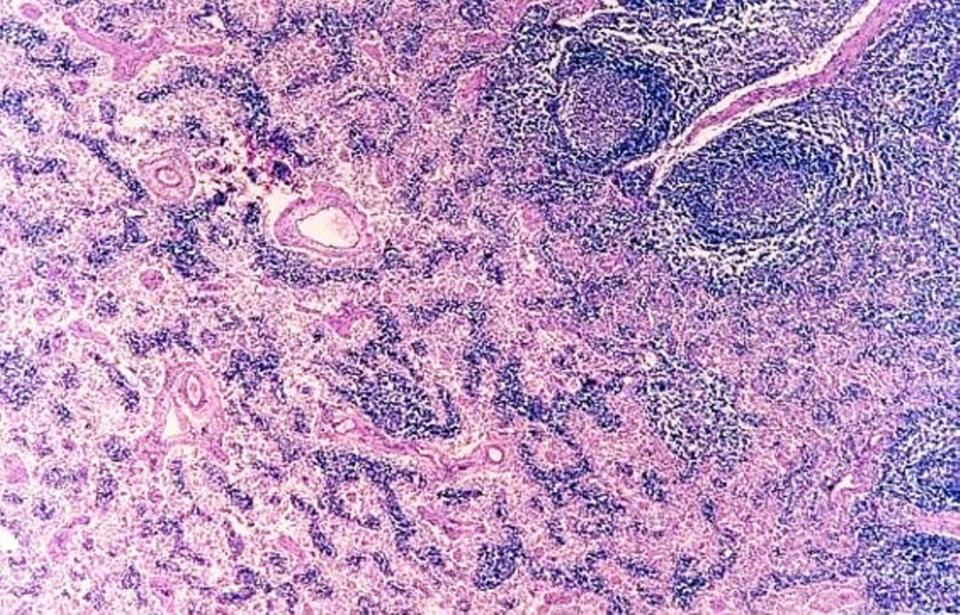

Próstata (glándulas tubuloalveolares compuestas; estroma fibromuscular;

Conductos